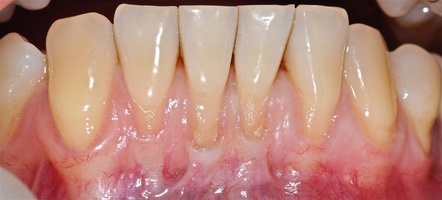

Послеоперационный период после всех операций протекал спокойно, без воспаления и особенностей, реактивный отек соответствовал норме в случае применения аутотрансплантата и ТМО (dura mater).

Реактивность в области применения ТМО и аутотрансплантата была сопоставима и сравнима с травмой мягких тканей при хирургическом вмешательстве. Имеет место реакция в обоих случаях на операцию, но на материал ТМО реакция отсутствует.

Во всех случаях применения аутотрансплантата и ТМО (dura mater) наблюдается сопоставимый положительный клинический результат по всем параметрам оценки рецессий десны (табл. 4). В случае нескольких зубов в области наиболее глубоких рецессий с наименьшими клиническими показателями имеет место сохранение класса рецессии не более первого класса (9 зубов) и глубиной не более 2 мм, 1.6 зуб — 3 мм.

В зарубежной литературе встречается также совокупный показатель эффективности лечения рецессий десны — процент закрытия корня зуба — отношение разница между конечным и исходным значениями глубины рецессии к исходному значению в процентах. Положительный результатом лечения является значение равное или более 80% [4]. Использование только показателя глубины рецессии десны для анализа эффективности лечения без учета остальных показателей (ТКД, ШКД, РРД, ЗДК) не дает полной картины результата и может быть применимо только в совокупности с другими показателями (рис. 6а-й).

Так в нашем случае процент закрытия корня зуба наблюдается больше 80% у 13 зубов. Менее 80% — у 11 зубов. Это связано с сохранением класса рецессии после лечения в области зубов с наибольшим классом рецессии и наибольшим показателем глубины рецессии. При этом средний показатель всех 24-х оперированных зубов — 83,1%. При этом среднее значение процента закрытия корня зуба для зубов с положительным результатом (более 80%) составляет 96,65%. Среднее значение для результатов менее 80% — 54,73, что связано с изменением глубины рецессий с 6 мм до 3 мм, с 4 мм до 2 мм и с 2 до 1 мм. При этом для аутотрансплантата и для ТМО результаты сопоставимы.